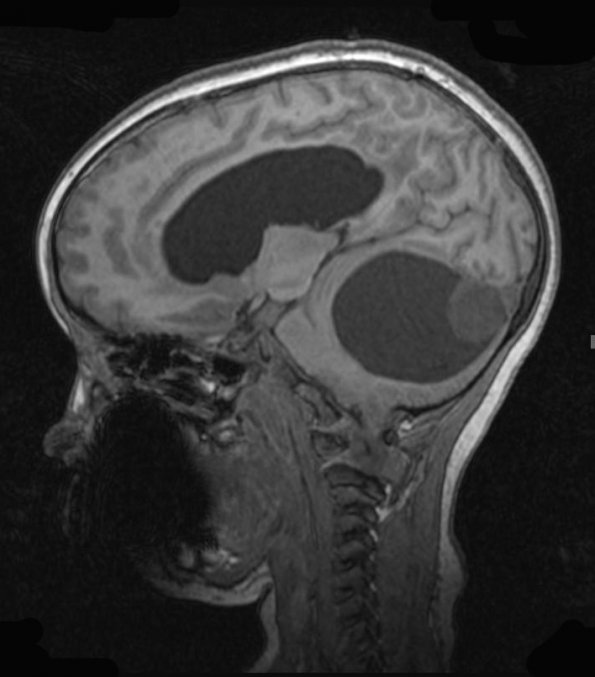

Case 22 ---- 7 year old female, cerebellum (No BRAF FISH fusion test available at WUSM) ----22A1-3 MRI examination of this cyst with mural nodule in the cerebellum is shown for T1-weighted scan (22A1), T1-weighted with contrast image (22A2) and T2-weighted with contrast (22A3)